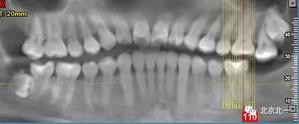

圖一:CBCT顯示右側下頜水平骨埋伏牙,牙冠距離下牙槽神經(jīng)管接近。

圖二:自帶的CBCT顯示下牙槽神經(jīng)管貼著智齒走形。

圖三:截面圖顯示神經(jīng)管位置。

圖九:重建后可見牙冠位于第二磨牙遠中,舌側傾斜。